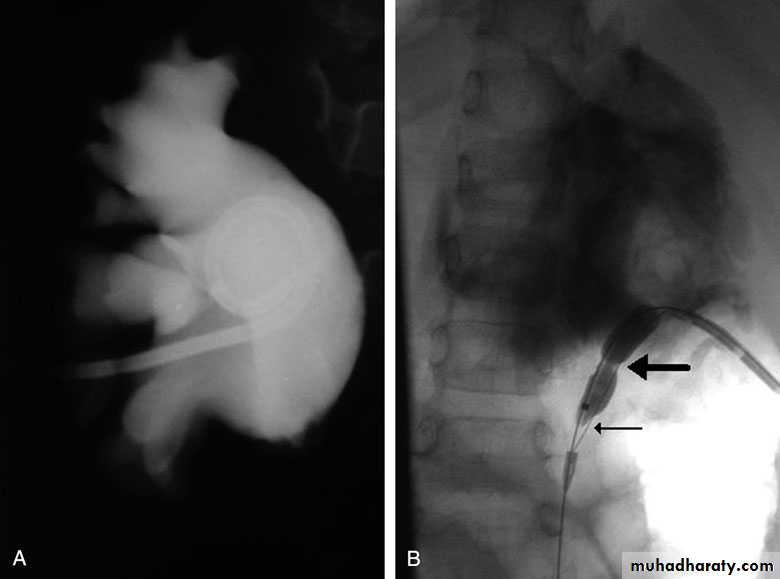

Open & laparoscopic surgical techniques Anderson-Hynes dismembered pyeloplasty: excision of the pathologic UPJ & appropriate reanastamosis or flap technique or flap operation

Endoscopic Approaches

balloon dilatationAntegrade endopyelotomy